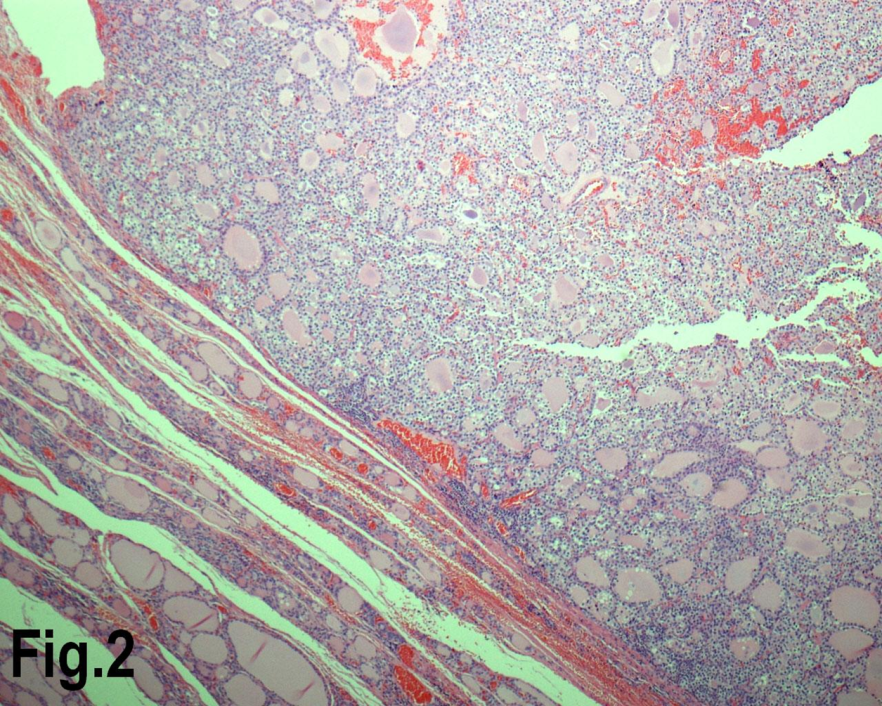

Figure 2.Low power view showing a follicular adenoma. (Hematoxylin & eosin, original magnification ×200).

Solitary benign adenomas were found in 23 cases, the peak frequency was fourth and fifth decade. Female accounted for 12 cases (70.5%) for follicular adenoma (Figure 2) and 3 cases (50%) for Hurthle cell adenoma. Thyroid malignancy and it was reported in 62 cases. Papillary carcinoma (Figure 3) was the most common type of thyroid malignancy found in 44 cases (71%) followed by follicular carcinoma (9.6%) (Figure 4), medullary carcinoma (1.6) and poorly differentiated carcinoma (1.6%) (Table 3). The peak incidence for patients with thyroid malignancy in this series was third decade and male to female ratio was 3.7:1.